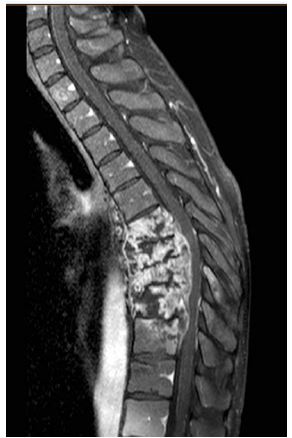

- CT scan showed: subverting of the lung parenchyma, presence of cavities in the superior lobes (Figure 1).

Given the inconclusive evidences of a pulmonary infection, a broncho-alveolar lavage was performed for standard cultural evaluation, Biofire Filmarray Pneumonia Panel and Koch Bacillus CRP research.

Figure 1: (Subverting of the lung parenchyma, presence of cavities in the superior lobes).